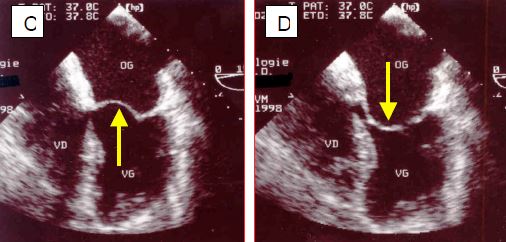

Figure 11.87 : Sténose mitrale (SM) lors de RAA (images ETO). A : vue 4-cavités ; l’OG est gigantesque, le VG est petit ; la fusion commissurale retient les feuillets en diastole et l’ouverture (flèche) est minime. B : fusion commissurale très serrée des deux feuillets. C : le corps du feuillet antérieur, resté souple dans le RAA, bombe dans l’OG en systole. D : le corps du feuillet antérieur bombe dans le VG en diastole (déformation en canne de hockey).